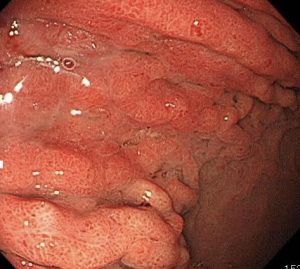

レントゲンで言われたように、胃の上部のひだが肥厚して腫れあがっています。

胃の壁は硬くなっていて、スコープで空気を入れてもこれ以上は広がりません。

これは「スキルス胃がん」です。

胃の粘膜下を這うようにしてがんが全体に進行するために、胃の壁が硬くなり広がらなくなります。

胃の上部から真ん中・出口近くまで、がんが粘膜下を這っています。